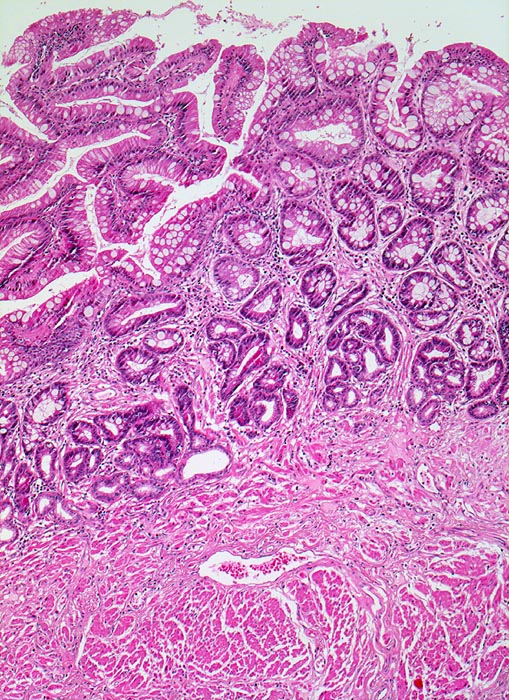

PathoPic – image database / PathoPic ID 4753 - Barrettmukosa

Barrettmukosa

Anstelle von Plattenepithel findet sich eine Zylinderzellmetaplasie mit Becherzellen, welche an Darmschleimhaut erinnert. Das Stroma der Lamina propria ist locker entzündlich infiltriert.

An anderer Stelle im Resektat kann neben schwer dysplastisch veränderter Barrett Mukosa ein Frühstadium eines invasiven Adenokarzinoms nachgewiesen werden.

Der alleinige Nachweis einer Zylinderepithelmetaplasie reicht nicht aus für die Diagnose eines Barrett Ösophagus. Die Bezeichnung Barrett Ösophagus ist Fällen mit Zylinderepithelmetaplasie mit Becherzellen(=spezialisiertes Epithel bzw. intestinale Metaplasie) der Ösophagusschleimhaut vorbehalten. Die Barrettmukosa kann zusätzlich eine leichte oder schwere Dysplasie aufweisen verbunden mit einem erhöhten Risiko für die Entwicklung eines Adenokarzinoms.